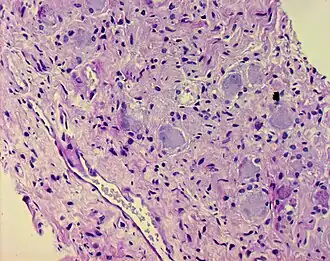

Ganglioneurome treten häufig als gut umschriebene, rundliche oder gelappte Tumoren von fester Konsistenz in Erscheinung. Die Schnittfläche erscheint grau-weiß bis gelb-grau und kann zystische oder verfettete Areale sowie Verkalkungen zeigen. Histologisch finden sich spindelige Zellproliferate (Schwann-Zellen) ähnlich wie bei einem Neurofibrom, wobei jedoch zusätzlich an Ganglienzellen erinnernde ganglioide Tumorzellen, häufig in Gruppen gelagert und mehrkernig, zu erkennen sind. Fokal werden häufig lymphozytäre Infiltrate sichtbar. Nekrosen fehlen üblicherweise.[5] Es wird als Zeichen der Gutartigkeit bewertet, dass die Tigroidschollen der ganglioiden Zellen noch erkennbar sind und somit keine Chromatolyse vorliegt.[6]